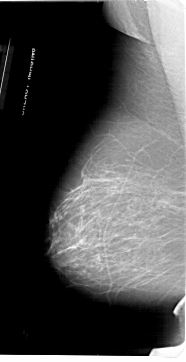

A_1953_1.LEFT_MLO

LEFT_MLO LINES 6871 PIXELS_PER_LINE 3526 BITS_PER_PIXEL 12 RESOLUTION 43.5 NON_OVERLAY